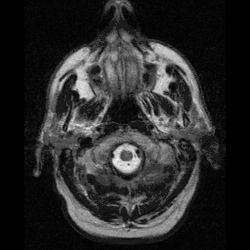

O campo da neurotecnologia existe desde a primeira metade do século XX, mas tornou-se maduro somente em meados da década de 1980. A representação do cérebro por imagens revolucionou a área e estimulou o início de várias pesquisas visando o monitoramento direto de áreas do cérebro durante a realização de experimentos. De medicamentos farmacêuticos à varredura cerebral, a neurotecnologia passou a afetar diretamente a qualidade de vida da população de forma direta ou indireta, seja pelo uso de drogas como antidepressivos ou de exames da atividade cerebral.[2]

- Imagem